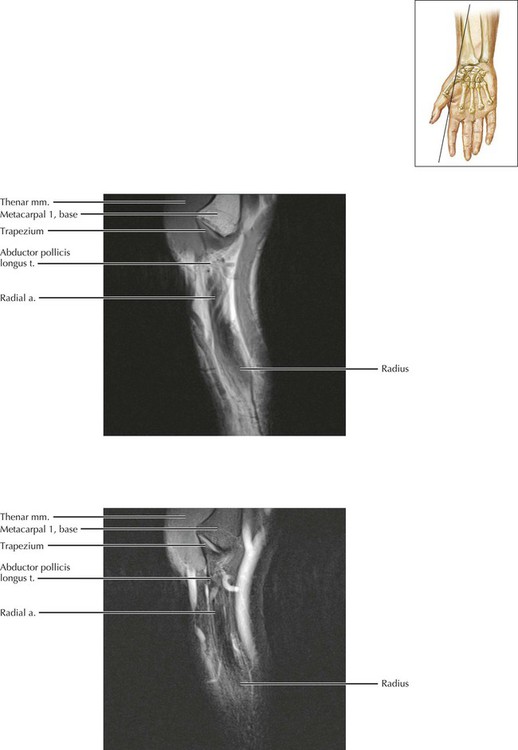

From radiologykey.com

IMAGING OF THE WRIST Radiology Key Wrist Compartments Radiology The ligament is divided into six extensor compartments, separated by. Each is separated by a reflection of the overlying extensor retinaculum. Keeping the patient’s wrist halfway between pronation and supination, place the probe over the lateral aspect of the radial styloid to examine. This article reviews the relevant anatomy and abnormalities affecting each of the six dorsal compartments of the. Wrist Compartments Radiology.